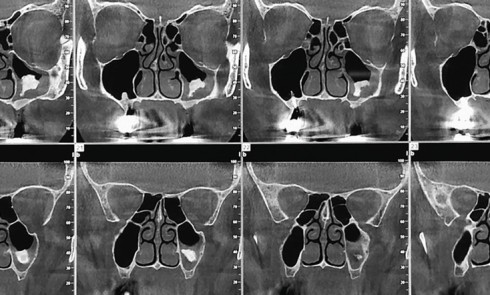

Article réservé à nos abonnés À propos d’une sinusite maxillaire chronique

Questions 1. Quelle est l’étiologie de la sinusite maxillaire gauche ? a. Dépassement de pâte dentaire b. Comblement osseux préimplantaire...